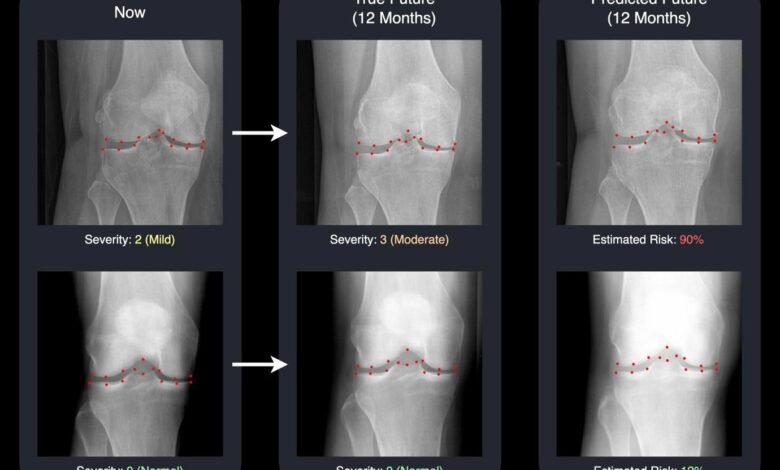

AI predicts osteoarthritis progression. Credit: University of Surrey

The findings were presented at the International Conference on Medical Image Computing and Computer Assisted Intervention (MICCAI 2025). The study explains how the Surrey team uses advancedmachine learningto produce a realistic “future” knee X-ray together with a score that estimates how likely the disease is to progress. When viewed together, these results give both doctors and patients a clearer and visual sense of what may lie ahead.

The system relies on a type of generative AI known as a diffusion model. It creates a projected future knee X-ray and marks 16 key points within the joint. By showing exactly which areas the AI is tracking for change, the system becomes transparent and easier for clinicians to understand and trust.